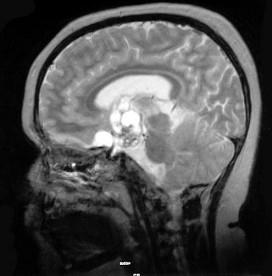

问题 关于颅咽管瘤(见图)的发生,以下哪项正确()

选项 A.儿童鞍区最常见的肿瘤 B.颅咽管正常在出生后7~8周退化消失 C.境界明显,有包膜 D.鞍内型最常见 E.小儿颅咽管瘤组织学多为鳞状表皮型

答案 A